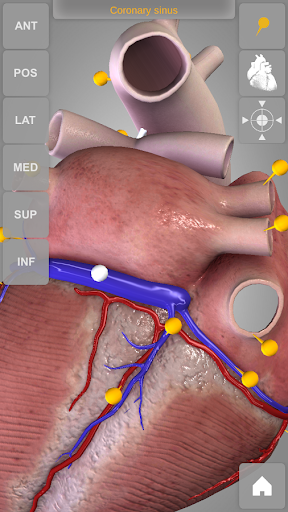

The human heart anatomical 3D model is revolvable in any direction giving a 360° view of the object.

User can choose external view or section view. Moreover, the names of specific anatomical areas can be shown touching the related pins (available in the full version only).